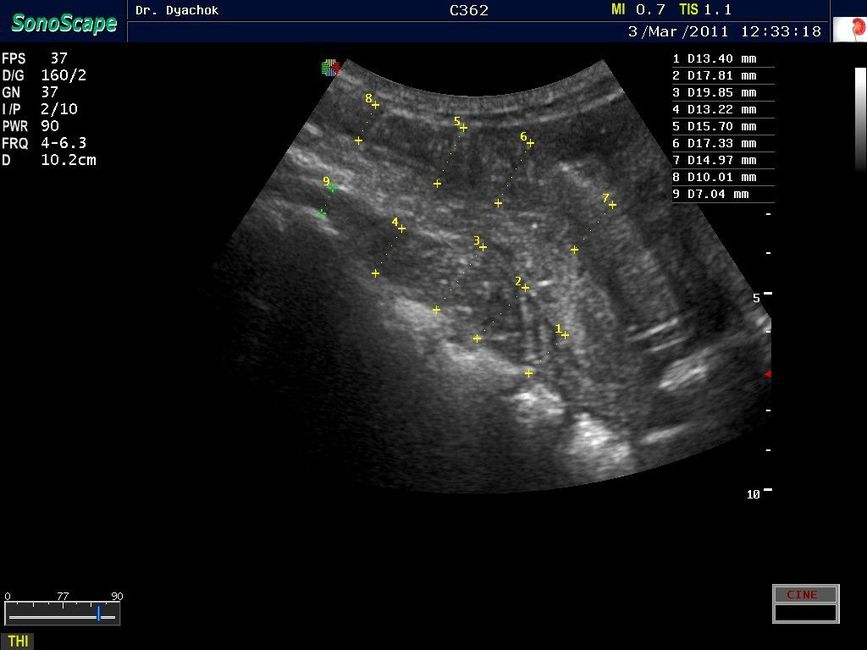

Sonoscape S9 представляет собой топовую переносную ультразвуковую систему, сочетающую инновационный дизайн, современные технологии визуализации и широкие диагностические возможности. Компактный аппарат экспертного класса подтверждает лидирующие позиции компании на рынке портативных ультразвуковых систем.

• Базовые режимы: B, M, B/M, B/B, 4B с поддержкой тканевой гармоники

• Технология Compound Imaging для многоракурсного формирования изображения

• Технология подавления спекл-шума MicroScan для повышения четкости изображения

• Трехмерная визуализация: режим FreeHand 3D для поверхностной реконструкции и 4D-режим для визуализации в реальном времени

• Панорамное сканирование

• Соноэластография с количественной оценкой

• Поддержка работы с ультразвуковыми контрастными веществами